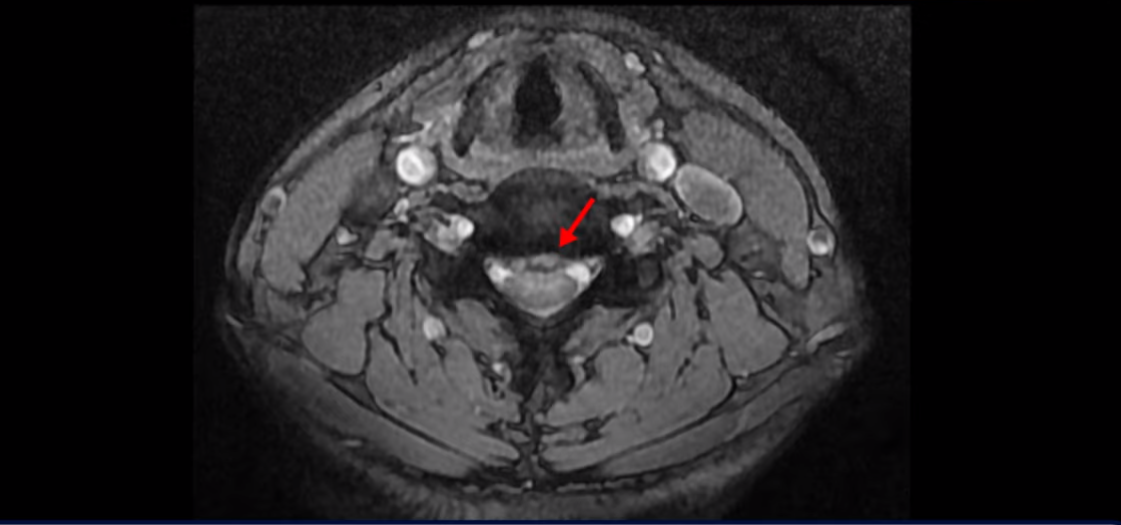

그런데 이 환자분의 방사통은 왼쪽 어깨와 팔입니다. 그래서 이 4번 5번 디스크 파열은 왼쪽 방사통의 원인이 아닌 걸로 보입니다. 6번 7번을 보면 디스크가 왼쪽으로 밀려 나와 있고, 뼈도 자라나 있습니다.

이렇게 뼈가 자라나 있으니까, 신경가지가 빠져나가는 추간공을 보면 여러 마디가 다 좁아져 있습니다.

이런 걸 협착이라고 합니다. 목이 협착이 진행된 것이죠. 그런데 왜 목디스크, 목 협착 치료가 허리보다 훨씬 더 쉽고 빠르다고 하는 걸까요? 그 이유는 목은 하중을 허리보다 훨씬 더 적게 받기 때문입니다. 하중을 적게 받으니까 신경 눌림이 조금만 줄어도 증상이 훨씬 더 빠르게 좋아지는 것입니다.